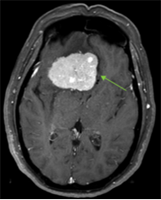

Mrs. Ramirez – Patient receives successful partial breast irradiation

This 68 year old otherwise healthy woman had a successful left breast lumpectomy for early stage breast cancer. At the beginning of her treatment she said, "I’m the only sitter all day for my five grand babies, I can’t come for 4-6 weeks of daily radiation treatment.”

Radiation therapy is generally required for the safe preservation of the breast and optimal cure rates after lumpectomy for breast cancer. Standard radiation therapy in this setting consists of 4-6 weeks of daily therapy to the entire breast. This treatment protocol is unfortunately inconvenient or prohibitive for many working women, those with child care responsibilities, or a large percentage of patients living far from radiation therapy centers or no transportation options.

For appropriate patients however, an advanced form of radiotherapy called partial breast irradiationor “brachytherapy (Greek derivation for “close therapy”) can be employed at experienced centers, targeting only the lumpectomy cavity anda “safety margin” of tissue in the breast. Because of the decreased normal tissues and organs exposed to radiation, the overall treatment time is reduced to five days of therapy, vs. 4-6 weeks of daily treatments.

After discussion of all options, including deferral of radiation therapy, an advanced partial breast radiation plan was designed for Mrs. Ramirez, allowing her to complete her treatment in a few days as opposed to several weeks. She tolerated the treatment well with no complications and returned to the care of her grandchildren as a full time nanny.